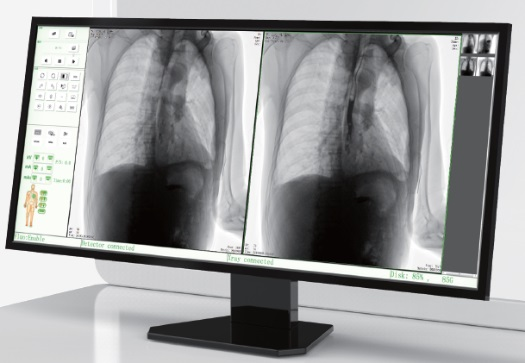

高品質(zhì)影像鏈 讓您看的更清晰 PLX8500C/D

● 無縫對接醫(yī)院PACS系統(tǒng),幫助實現(xiàn)信息共享、遠(yuǎn)程診斷。